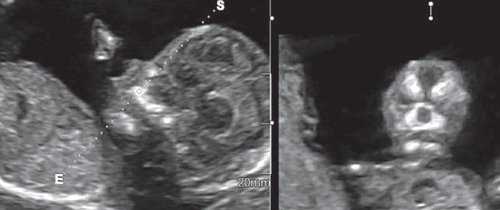

При эхографии в срок 13 недель 3 дня фетометрические параметры плода соответствовали гестационной норме, толщина воротникового пространства составила 1,5 мм; длина костей носа - по 2,5 мм. При трансвагинальном сканировании были обнаружены: затылочное энцефалоцеле размерами 7,4х3,5х3,7 мм (рис. 1), полидактилия кистей (рис. 2), увеличенные кистозно-измененные почки: правая - 28,5х21,3 мм; левая - 26,4х18,7 мм (рис. 3). Объем амниотической полости был нормальным для данного срока.

(Слева) Тот же плод. УЗИ брюшной полости, фронтальная плоскость. С обеих сторон определяются увеличенные кистозно-измененные почки. Необходимо помнить, что объем амниотической жидкости в I триместре может быть в норме, даже несмотря на тяжелое двустороннее поражение почек.

(Справа) Во время скринингового УЗИ плода в I триместре, выполненного во время последующей беременности у той же женщины, обнаружено энцефалоцеле. Синдром Меккеля-Грубера имеет аутосомно-рецессивный тип наследования, риск повторного возникновения составляет 25%.